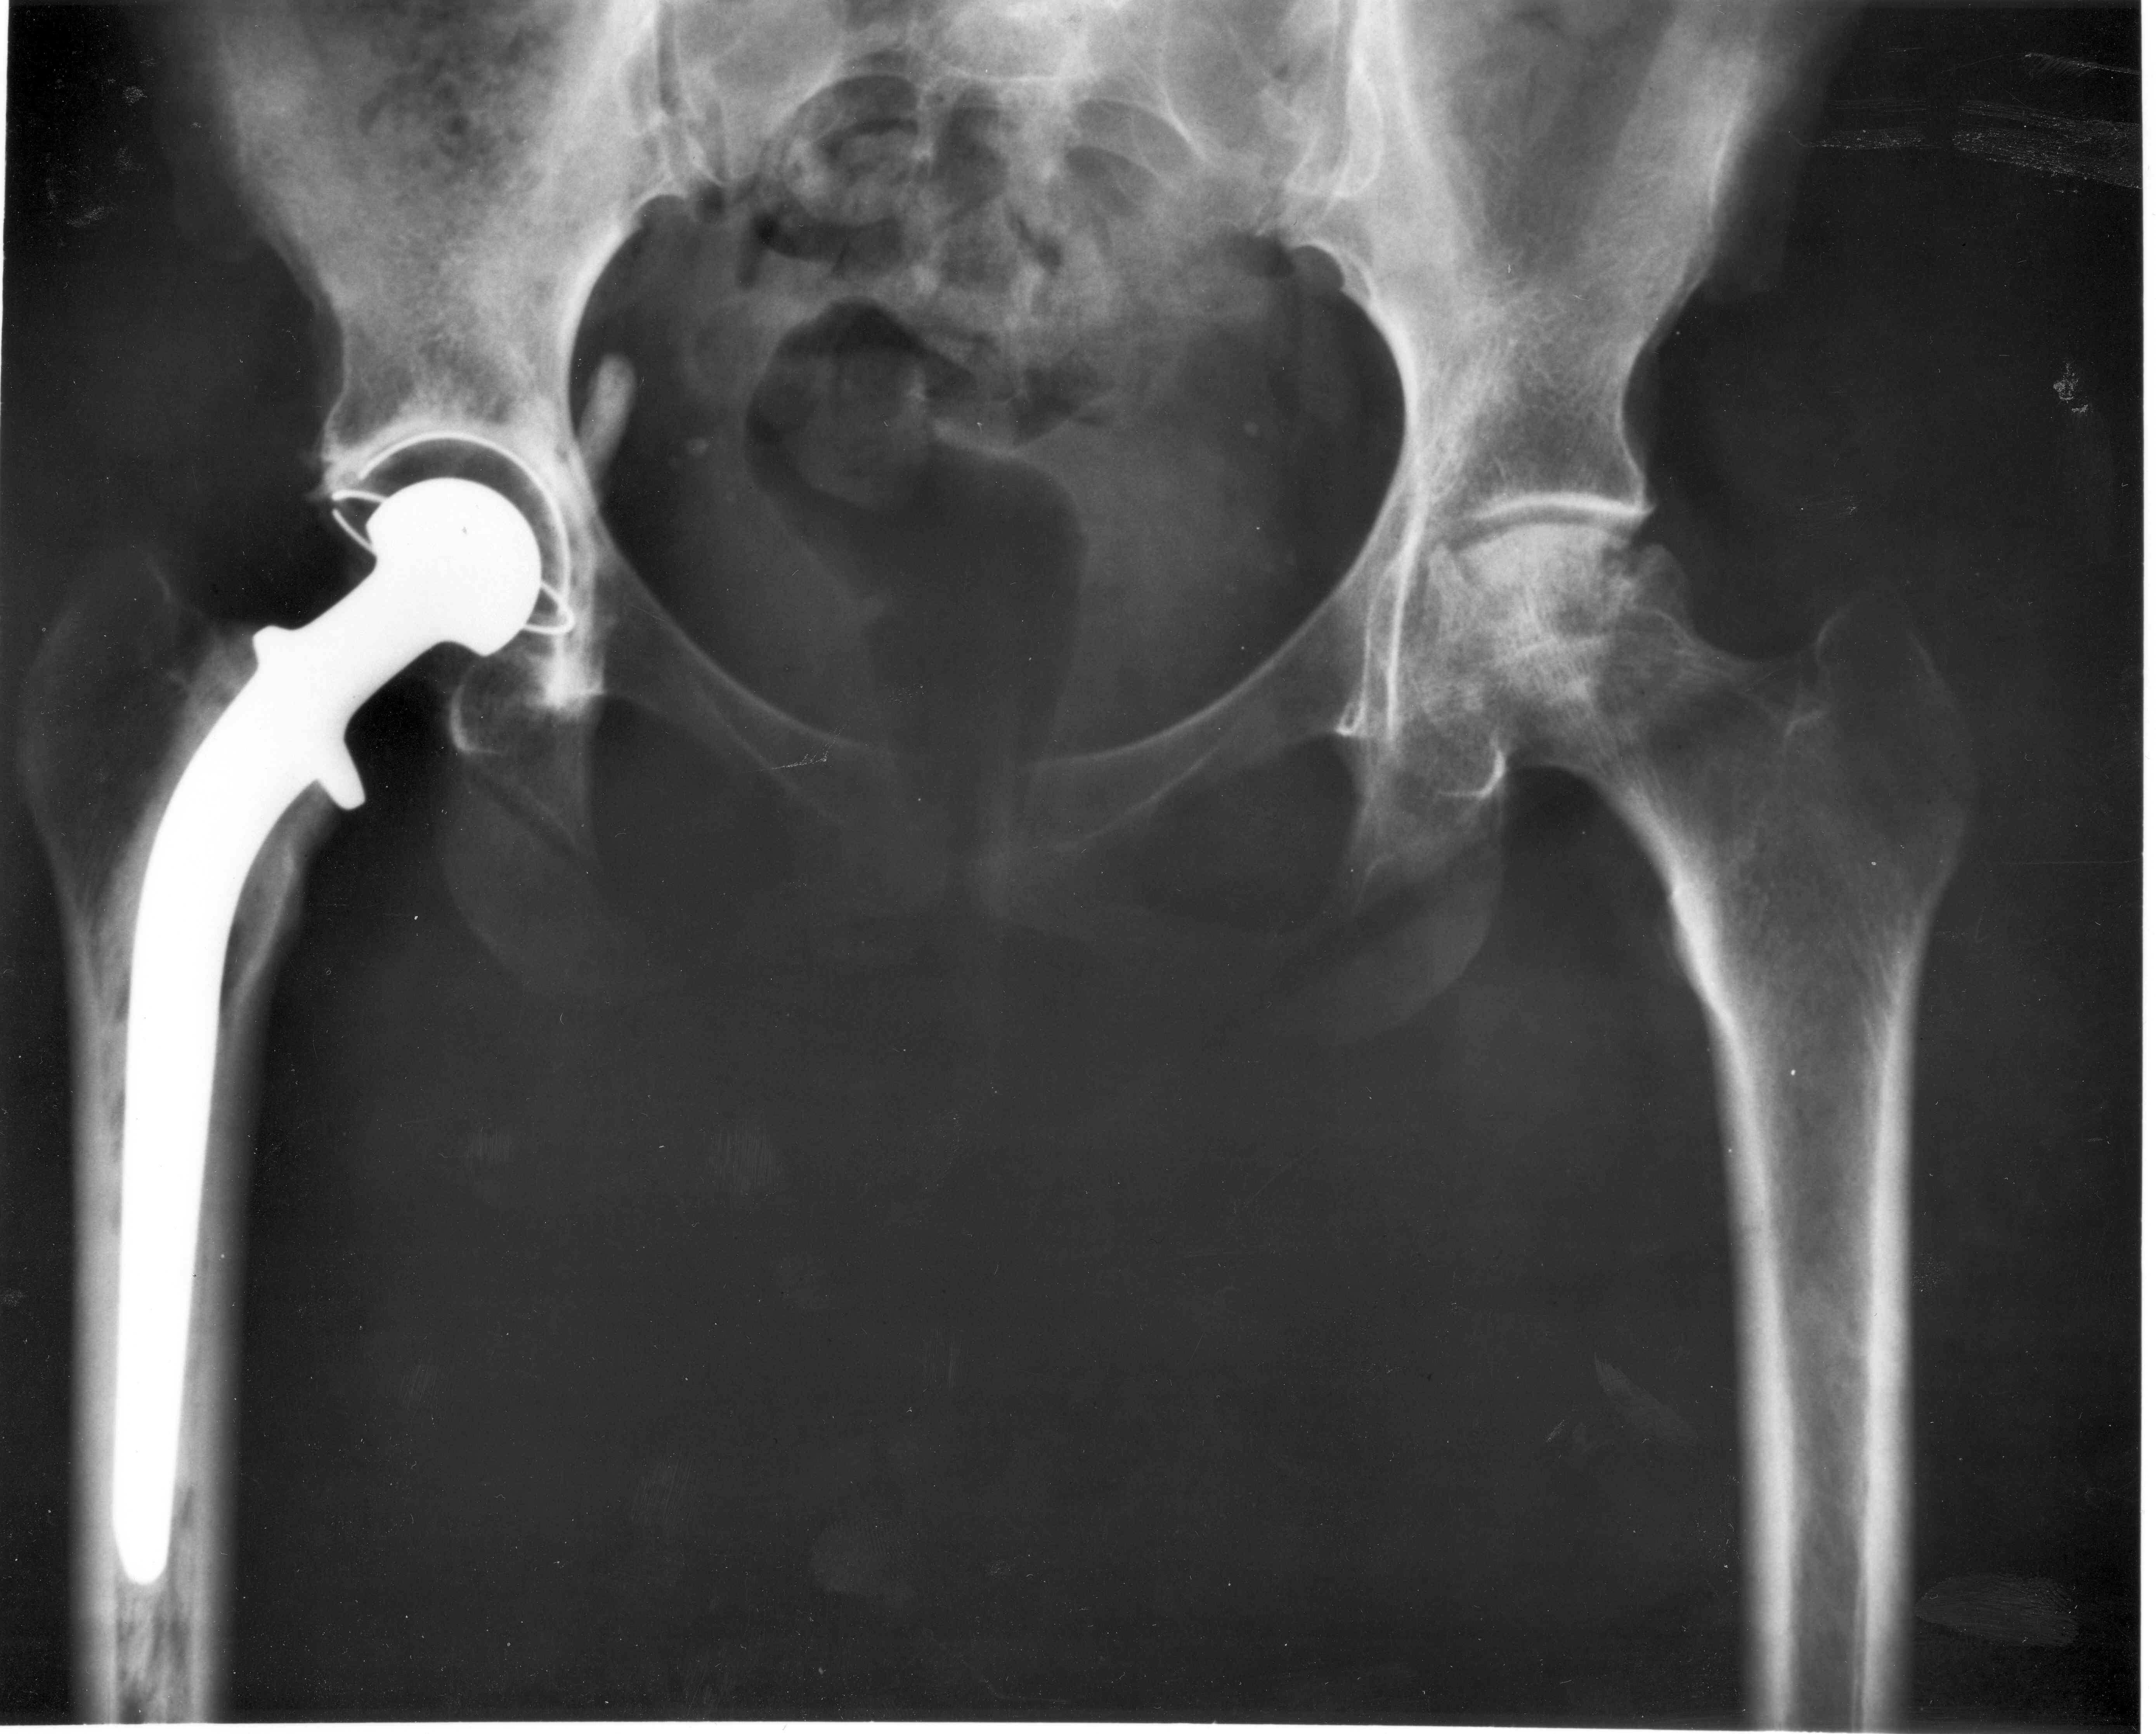

현대 고관절 치환술은 1960년대 영국의 존 찰리(John Charnley) 경에 의해 개척되었다.[10] 그는 관절 표면을 뼈에 시멘트로 고정한 임플란트로 대체하는 방법을 개발했다. 찰리의 디자인은 스테인리스 강 대퇴부 줄기와 머리, 폴리에틸렌 비구 구성 요소를 PMMA(아크릴) 뼈 시멘트로 고정하는 방식이었다. 엑서터 고관절 치환술 시스템도 개발되었다. W. H. 해리스와 그의 팀은 뼈가 직접 결합하는 비시멘트 관절 성형술 기술을 개척했다.

존 찰리는 1960년대 고관절 치환술을 개척하여 현대 고관절 임플란트의 기초를 마련했다.[10] 1970년대에는 무릎 관절 치환술이 시작되었으며, 존 인설은 고정 베어링 시스템을, 프레데릭 부쉘과 마이클 파파스는 이동 베어링 시스템을 개발했다.[11]

존 찰리는 1960년대 고관절 치환술을 개척했다.[10] 그는 관절 표면을 뼈에 시멘트로 고정한 임플란트로 대체하는 방법을 개발했다. 찰리의 디자인은 현대 고관절 임플란트의 기초가 되었다. 엑서터 고관절 치환술 시스템도 개발되었으며, W. H. 해리스는 비시멘트 관절 성형술 기술을 개척했다.